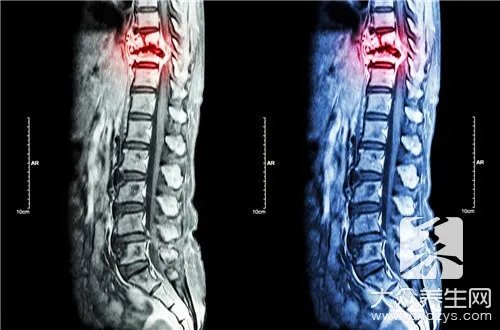

低温等离子消融术简介低温等离子消融术是美国军事科技开发的医疗仪器,属于第四代物理治疗技术,1999年美国FDA批准后开始在临床中广泛应用。低温等离子射频消融术式通过在C形臂或CT引导下,医生将穿刺针插入椎间盘内,然后通过等离子刀将射频能量作用于椎间盘,将刀头周围组织的分子键打断形成离子态,简单来说就是将周围组织气化,通过反复消融可将对神经造成压迫的组织全部气化排出体外。整个消融过程刀头温度维持在70℃,离开刀头1mm,温度即降为40℃,所以对周围神经造成损伤的可能性非常小。同时还可以利用等离子刀的冷凝固作用,使消融通道周围组织皱缩,固化,防止髓核组织沿消融通道再次突出。消融过程仅需数分钟,整个手术过程也不会超过1小时,而且手术在局麻下进行,患者有任何不适都可以第一时间与术者交流。使得神经损伤的可能性进一步下降。